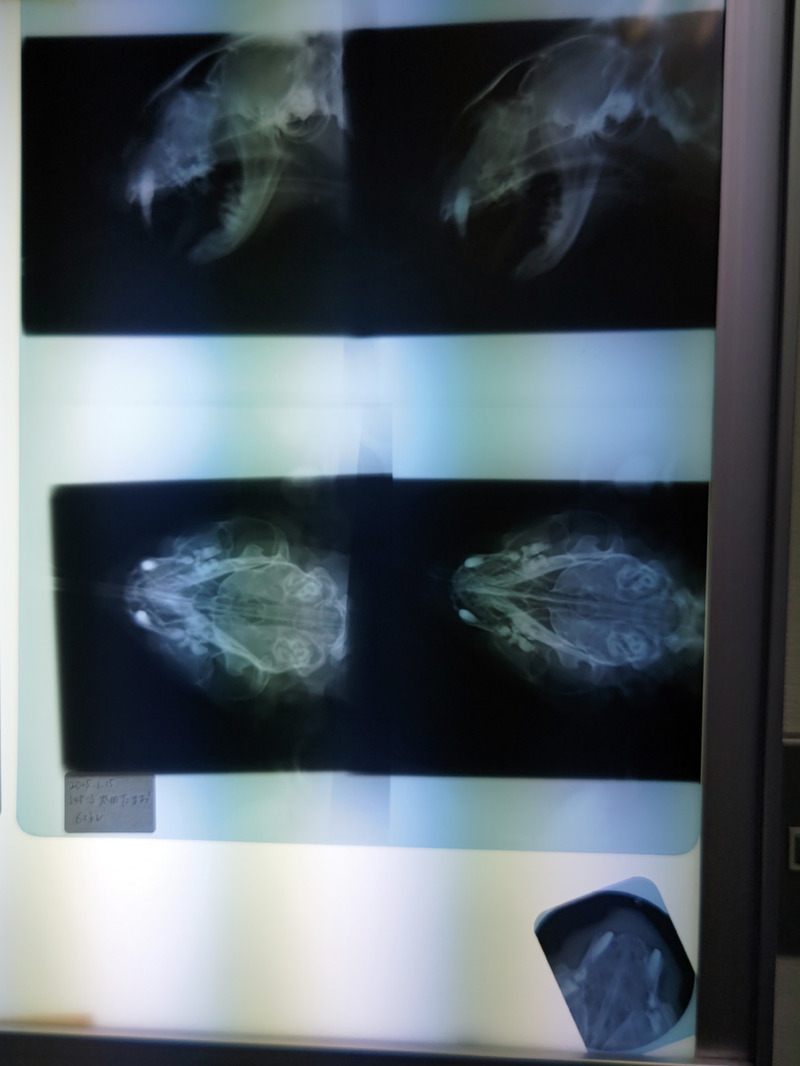

病理検査の報告書です

病理検査の結果が出ていました

まず耳下の腫瘍は良性で問題なし

しかし鼻部分の腫瘍はリンパ腫ということで

悪性という結果

そして今日がその1週間後

l8926

今日 午前9時半

たまおは午後に麻酔をかけられ

いろいろ調べてもらいます

l8939

夕方6時

たまおをお迎えに行ってきました

幸い腫瘍は骨まで達していません

l8953

耳の下にも腫瘍が出来ていました

ついでに取っておきましたよと先生

l8963

鼻の上を切開

腫瘍の一部を切り取って病理検査へ

検査結果が出るまでさらに1週間

結果次第で たまおの運命が決まります